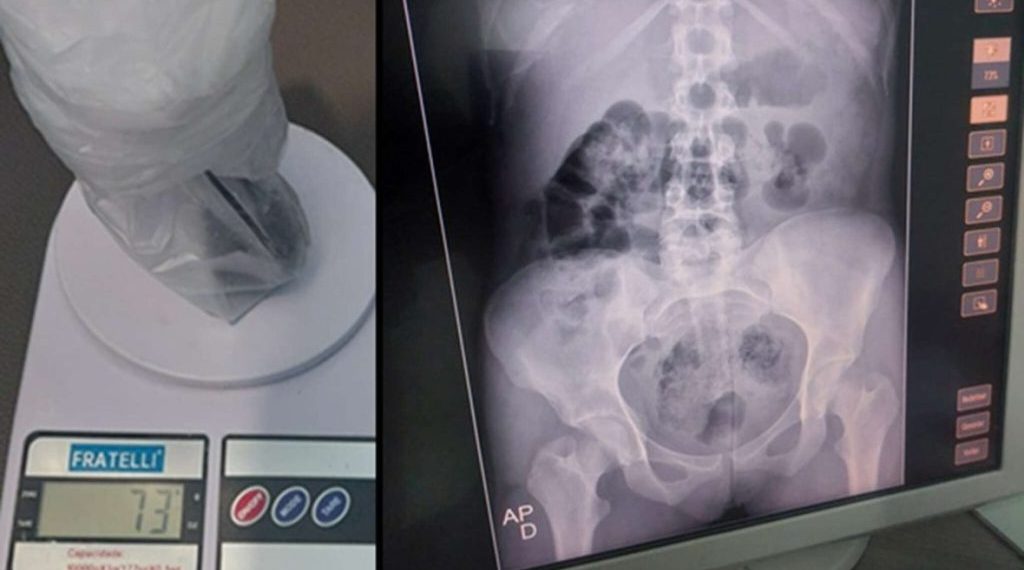

Duas mulheres foram presas, neste sábado (20), tentando levar pacotes com drogas escondidas nas partes íntimas para dentro da Penitenciária Padrão de Cajazeiras.

De acordo com a direção do presídio, uma das mulheres carregava dois pacotes nas partes íntimas, sendo um deles 50 gramas de maconha e o outro com um pouco mais de 50 gramas de cocaína.

As mulheres foram levadas para o Hospital Regional de Cajazeiras (HRC) para retirada dos entorpecentes. Uma delas deve ser submetida a um procedimento cirúrgico devido ao volume considerável de drogas.